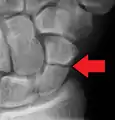

A subtle scaphoid fracture

A more obvious scaphoid fracture on a scaphoid view X ray